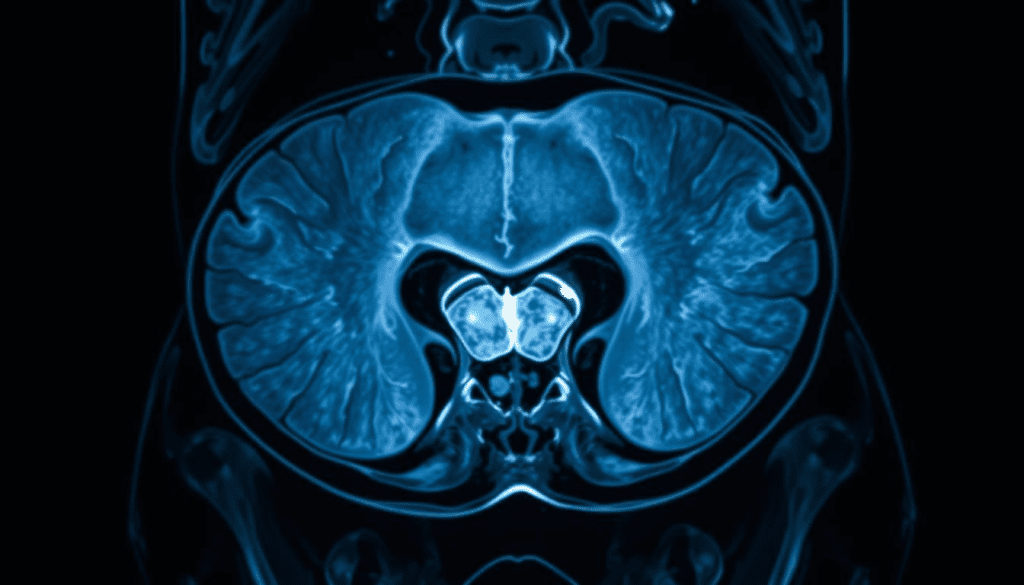

How MRI Technology Visualizes the Bladder

MRI technology has changed how we see and diagnose bladder problems. It gives us clear and detailed images. At its heart, MRI technology uses a strong magnet and radio waves. These create detailed pictures of the body’s inside, like the bladder.

MRI works by using a strong magnetic field. This field makes hydrogen atoms in the body line up. Then, radio waves disturb these atoms, sending signals to the MRI machine. These signals help make detailed images.

This method is great for seeing soft tissues. It’s perfect for checking bladder health. Unlike CT scans, MRI doesn’t use harmful radiation. This makes it safer for patients needing many scans.